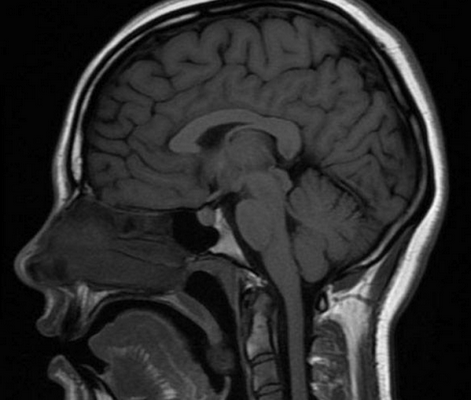

МР-сканирование при подозрении на менингиому мостомозжечкового угла, сагиттальная проекция